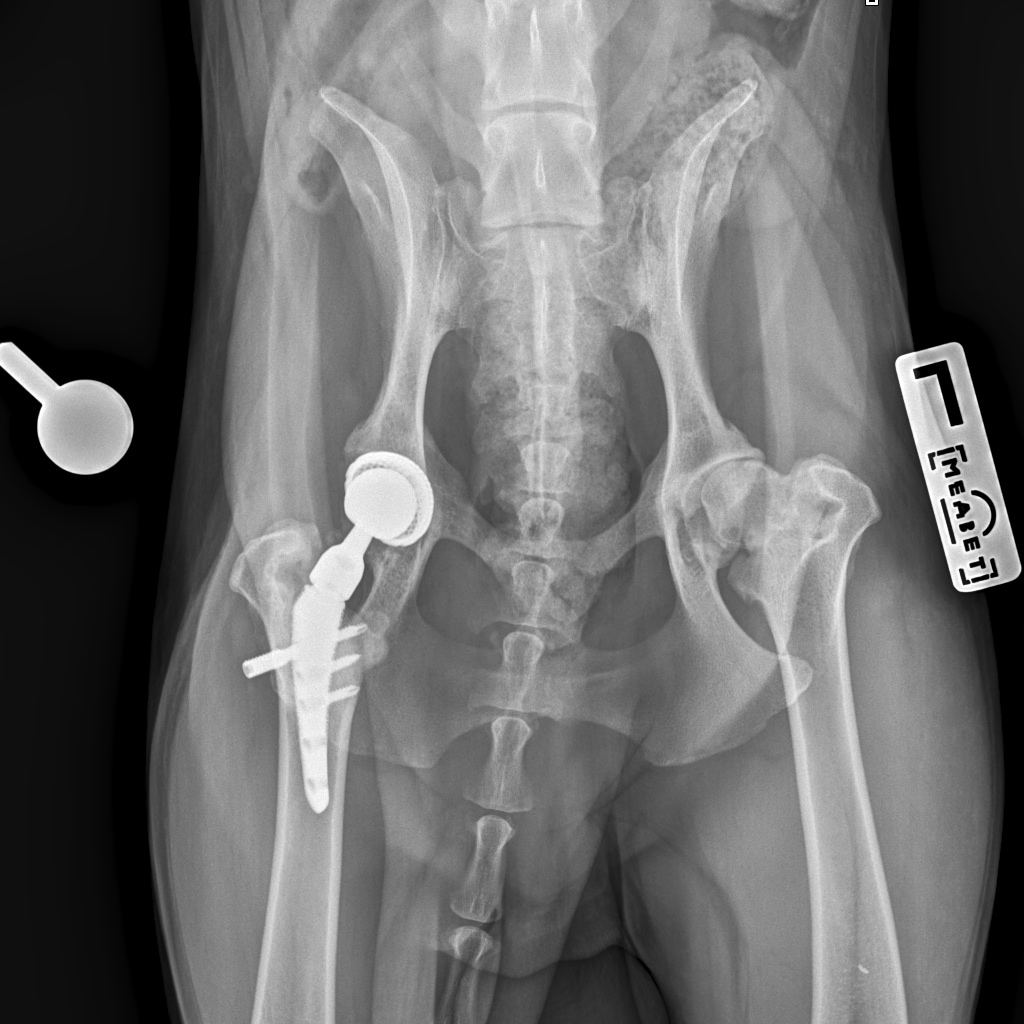

8A836050-66CA-42B2-94D3-F13B288A592B.jpeg

39B2671E-39B9-4502-9E11-ADB169612F24.jpeg

6950B9C9-79EA-4F34-A780-9C3C6BA31B49.jpeg

58C20B18-AA4E-4386-BF83-56CE5E282844.jpeg

Наш металлический мальчик

Железный дровосек